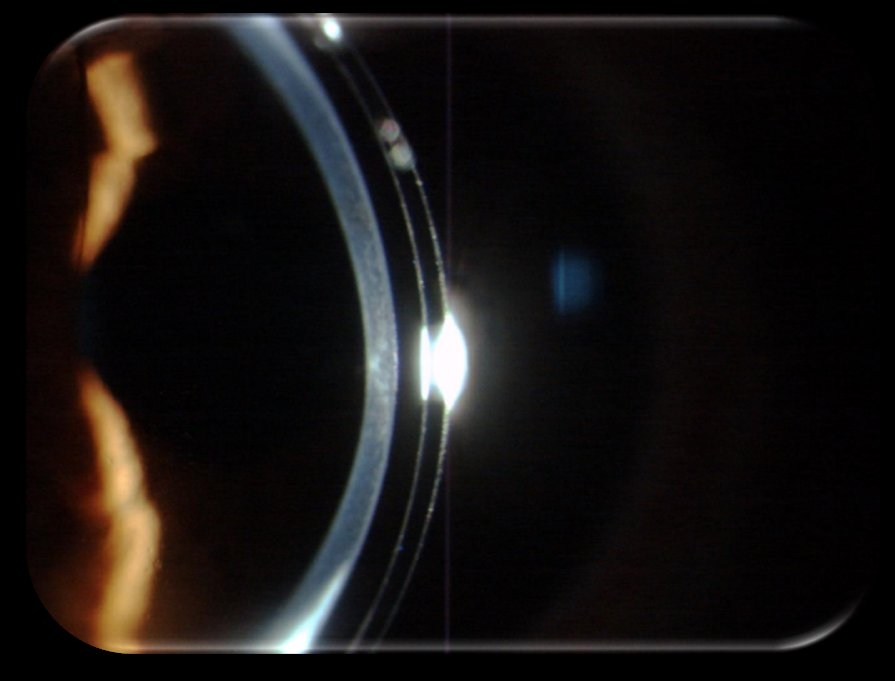

A investigação desenvolvida no CFUM abrange novos métodos de diagnóstico, estratégias para controlo da miopia e tecnologias óticas inovadoras, posicionando-nos na linha da frente nesta área. Além disso, há vários domínios com grande potencial de impacto: investigação sobre a película lacrimal e conforto com lentes de contacto, análise da pressão intraocular em relação às propriedades biomecânicas da córnea, estudos sobre visão das cores e perceção cromática em diferentes condições de iluminação e em indivíduos com dicromacia, e investigação em presbiopia, incluindo participação em revisões internacionais de referência como o BCLA CLEAR Presbyopia (2024). Estes trabalhos combinam inovação tecnológica com respostas a problemas clínicos e sociais relevantes.

A participação na rede OBERON, focada em desafios de opto-biomecânica e visão, amplia a nossa capacidade de dar respostas inovadoras e de formar especialistas nesta área. Podemos destacar projetos que atravessam várias frentes: estudos clínicos e laboratoriais sobre miopia e ortoqueratologia, lentes de foco estendido e biomarcadores. Estes exemplos mostram como o CFUM integra investigação fundamental, tecnológica e clínica, explorando múltiplas áreas com relevância social e científica.

Em particular, estamos envolvidos num grande projeto dedicado à investigação de novas soluções para baterias de lítio. Na área da visão, as contribuições do CFUM centram-se no desenvolvimento de métodos para o controlo da progressão da miopia, avaliação e melhoria do desempenho visual em diferentes contextos clínicos e digitais, e soluções óticas para presbiopia. Investigamos também a película lacrimal, o impacto das lentes de contacto, a pressão intraocular e as propriedades biomecânicas da córnea, bem como a perceção cromática em condições reais de iluminação e em indivíduos com dicromacia. Estes trabalhos têm aplicação direta em clínica, ergonomia visual e prevenção de síndromes como o “computer vision syndrome”.